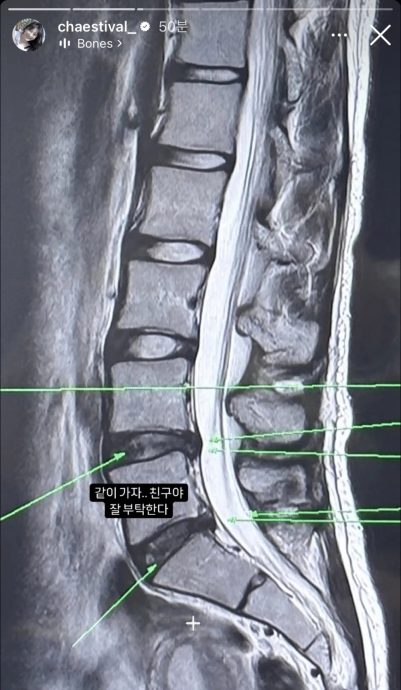

(首尔23日讯)24岁韩国女歌手李彩演2018年参加韩国选秀节目《Produce 48》,因坚强的舞蹈实力以限定女团IZ*ONE成员出道,在合约结束后便Solo出道,但她近日却传出腰部受伤的消息,并晒出腰椎X光照片,宣布将暂停跳舞一段时间,让粉丝感到担忧。

李彩演在IG限时动态分享自己的腰椎X光照片,透露因腰部不适前往医院检查。随后,又上传一段舞蹈练习视频,可见她完成了一些需要大幅度腰部动作的舞蹈,包括向后弯腰等高难度的姿势,并配文写道:“没坏掉真是神奇,辛苦了。”

据韩媒报道,李彩演的腰伤还不到椎间盘突出程度,现有的行程安排不会受到影响。她的经纪公司也回应表示,李彩演目前正在接受物理治疗。